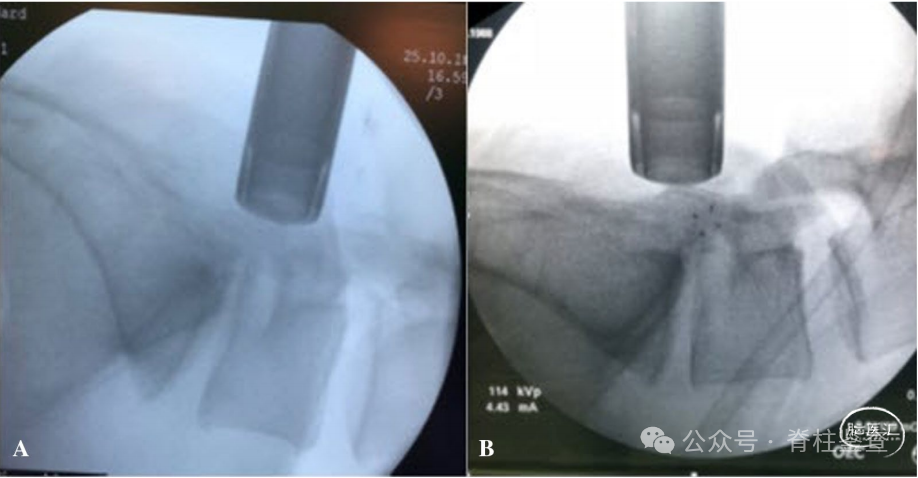

全麻下取俯卧位,使用上次手术切口,切口均距离中线1-1.5 cm之间。

磨钻磨除椎板,从椎板缺损边缘向上延伸以远离瘢痕。